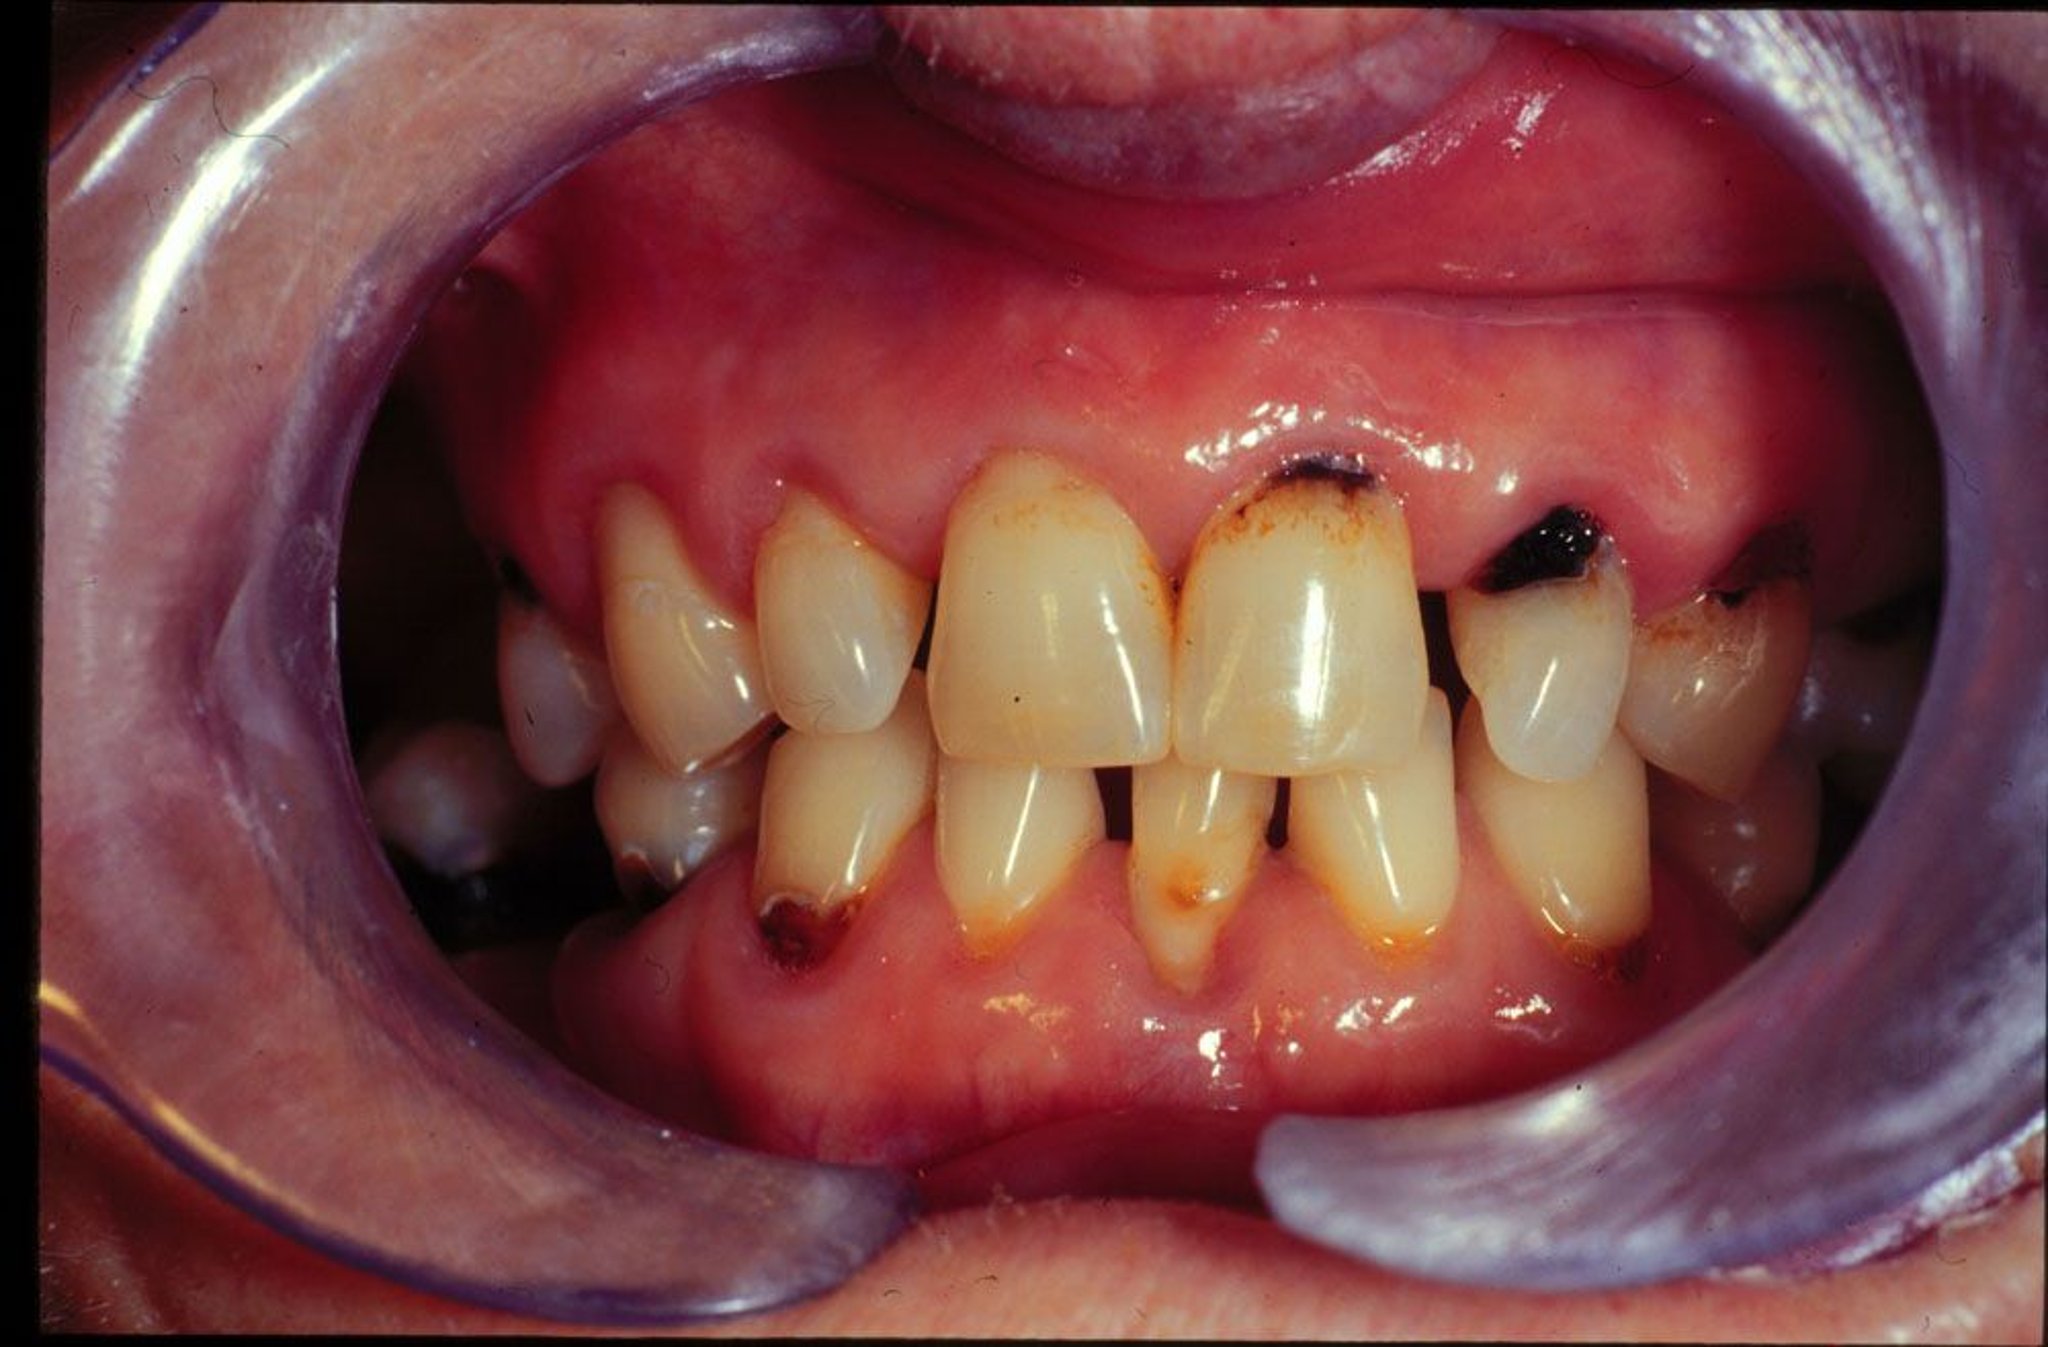

Neue und rezidivierende Zahnkaries bei einem Patienten mit trockenem Mund.

Image provided by Jonathan A. Ship, DMD.